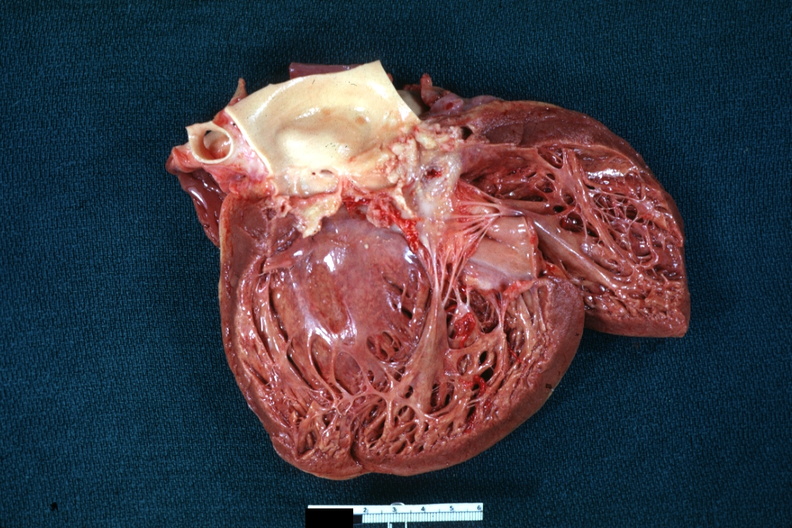

GROSS: CARDIOVASCULAR: HEART: Anemia: Gross excellent tigering also has thrombotic nonbacterial endocarditis on aortic valve but is not too well shown